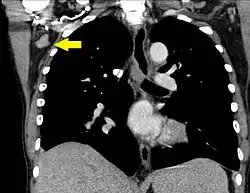

Mediastinum | |

Mediastinum, generally | 10 mm[31] |

Superior mediastinum and high paratracheal | 7mm[34] |

Low paratracheal and subcarinal | 11 mm[34] |